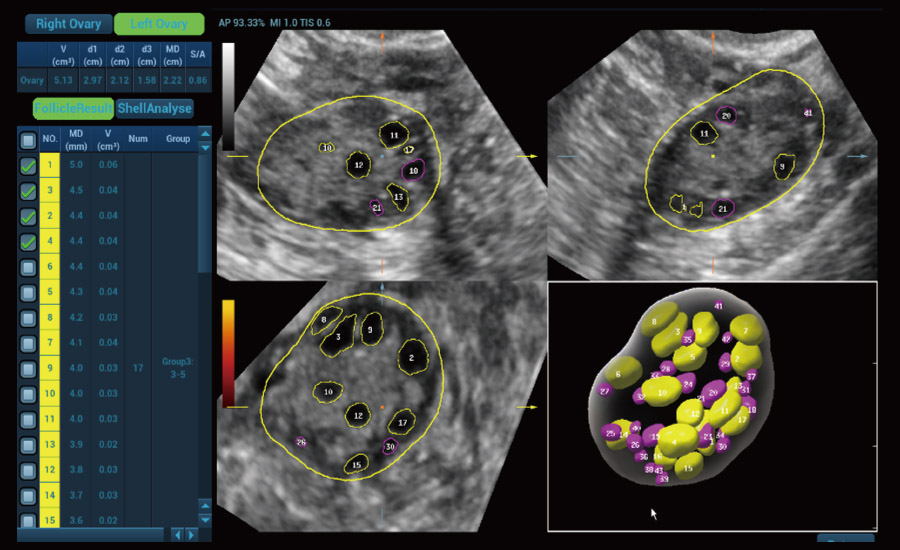

Fertilidade

Por meio da combina??o de algoritmos avan?ados e do conhecimento especĆfico da regi?o, a inovadora solu??o Smart Scene permite a identifica??o automĆ”tica das caracterĆsticas do tecido e fornece diagnĆ³stico especĆfico dos Ć³rg?os com informa??es completas. Com base na identifica??o automĆ”tica de cenĆ”rios, a solu??o realiza n?o apenas a varredura 2D inteligente com configura??es e medidas automĆ”ticas, mas tambĆ©m oferece informa??es 3D abrangentes em todas as etapas, desde a otimiza??o de imagens volumĆ©tricas atĆ© a difĆcil obten??o de planos 2D, e a quantifica??o durante todo o procedimento. Ele ajuda a reduzir em grande parte a dependĆŖncia de habilidades clĆnicas, ao mesmo tempo que aumenta a precis?o, a confian?a e a eficiĆŖncia no diagnĆ³stico.

Solu??es profissionais de ultrassom com informa??es abrangentes

- Protegendo novas vidas com solu??es em fertilidade e obstetrĆcia